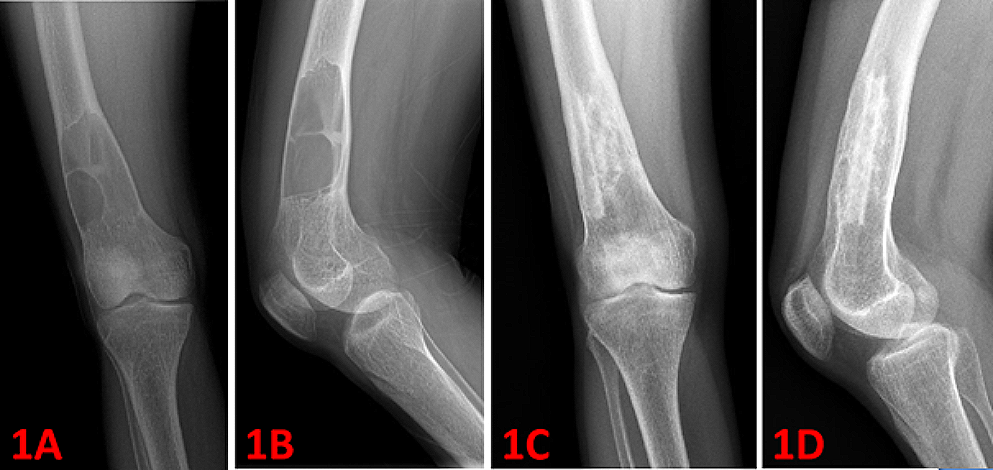

Fig. 1

A 18-year-old female with osteolytic lesion (brown tumor) in the right distal femur (1 A and 1B: preoperative radiograms). Curettage was performed, followed by iliac crest autografting and cancellous allografting was applied. Figure 1 C and 1D shows postoperative 12th months radiograms

The most common sites of localization were the pelvis, femur, ribs, tibia, proximal humerus, and mandible (Table 2). 7 patients (26,9%) had solitary lesions, while 19 patients (73,1%) had multiple lesions. A total of 65 lesions were observed in 26 patients. Orthopedic surgery was performed in 21 of 26 patients, the other 5 cases were followed up conservatively. Among the 65 lesions, 23 lesions (35,4%) underwent surgery, whereas 42 lesions (64,6%) were followed conservatively (Table 2). Intralesional curettage was performed in 19 cases (82,6%). The resulting cavity was filled with bone cement in 11 cases (47,8%). Bone grafting was applied in 8 cases (34,8%) (see Figs. 1, 2; Table 3).